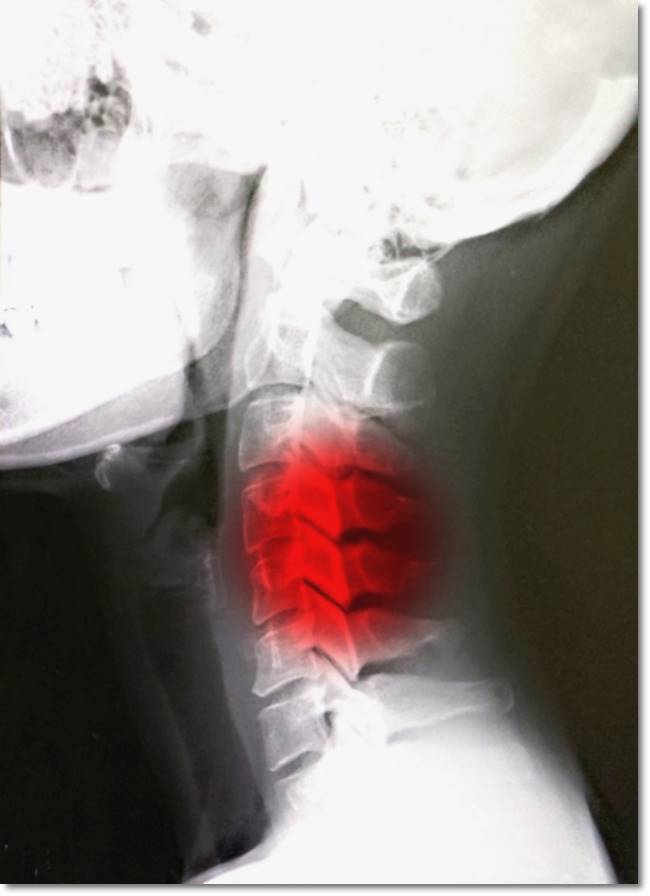

거북목 증상 치료방법 간단한 스트레칭 해주기

평소 잘못된 자세로 목, 어깨 근육과 인대가 늘어나 통증이 생기는 증상으로 평소 컴퓨터, 모니터를 많이 보는 직업, 낮은 위치에 있는 모니터를 내려다보는 사람에게 많이 발생합니다.

또 한시간 중에서 5~ 10분은 일어서서 가볍게 걸으면서 스트레칭을 해주는 것이 좋습니다. 거북목 증상이 오래되면 증후군으로 발전할 가능성이 크고 구부정하게 앉는 자세는 s자형의 척추를 일자형으로 만들어 허리 디스크에도 걸릴 수가 있으니 미리미리 관리를 해주는 것이 좋습니다.